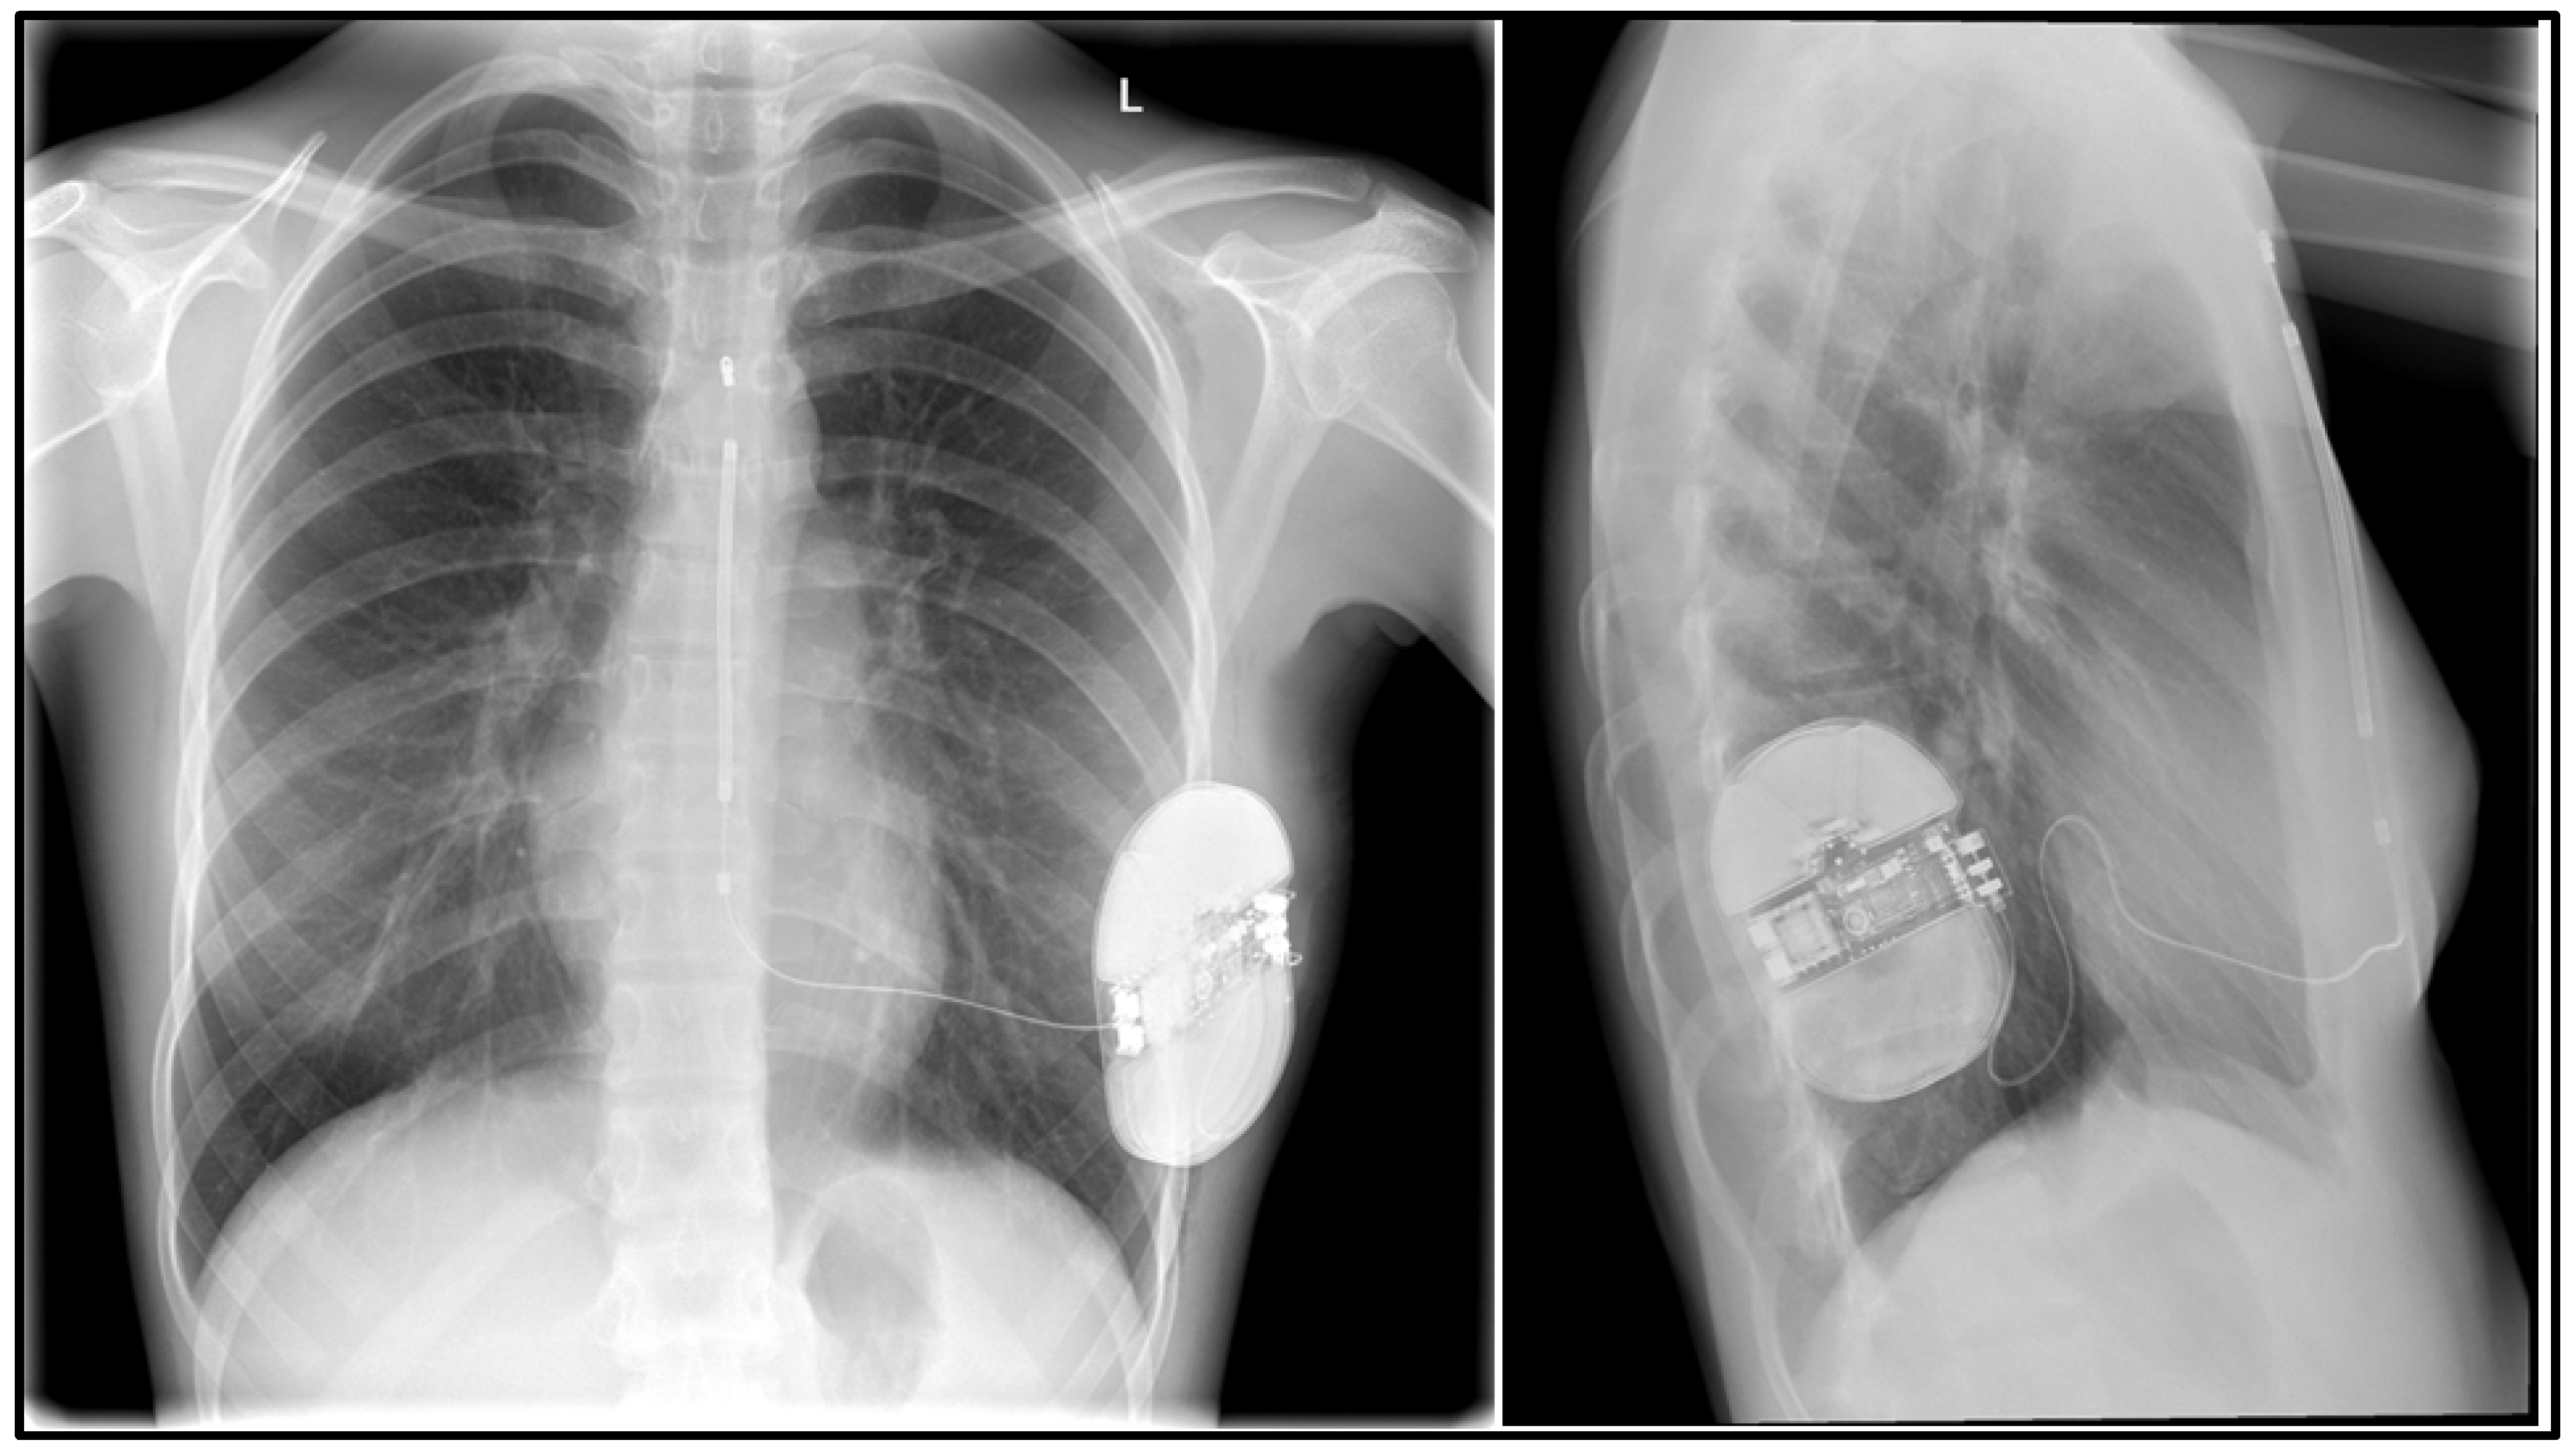

- A 16-year-old male patient diagnosed with Brugada syndrome, implanted with an ICD system, qualified for S-ICD implantation due to battery depletion and increasing defibrillation lead resistance. He had a history of several episodes of unconsciousness up to the age of 3 years and, at age 9 years, during an episode of SCA, the boy lost consciousness on the beach; he was assisted by a cardiologist present there, who started CPR. During hospitalization after the episode, he was diagnosed with Brugada syndrome. He was implanted with an ICD and one year after implantation, there was an episode of adequate defibrillation. It was decided that the transvenous system would be temporarily left and an S-ICD device implanted and, after healing, a decision would be made on the intracardiac lead removal.